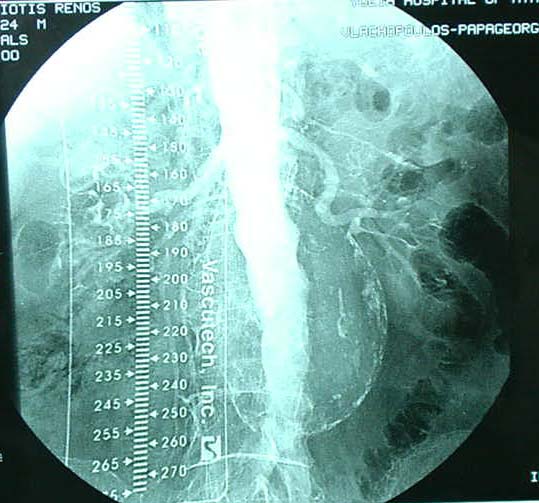

ÓõíÞèùò ç äéÜãíùóç ôïõ áíåõñýóìáôïò ãßíåôáé ôõ÷áßá ìåôÜ áðü êÜðïéá äéáãíùóôéêÞ åîÝôáóç üðùò áêôéíïãñáößá óôçí êïéëéÜ, áîïíéêÞ Þ ìáãíçôéêÞ ôïìïãñáößá êïéëßáò êáé êõñßùò áðü õðåñç÷ïãñÜöçìá Triplex , åéäéêüôåñá äå ìåôÜ áðü áããåéïãñáößá Þ õðåñç÷çôéêÞ ðáíáñôçñéïãñáößá.

1. Ç êëáóéêÞ áããåéï÷åéñïõñãéêÞ åðÝìâáóç ìå åêôïìÞ ôïõ áíåõñõóìáôéêïý óÜêïõ ìå ôçí ôïðïèÝôçóç ðëáóôéêÞò áñôçñéáêÞò ðñïèÝóåùò áðü Dacron ç ïðïßá åßíáé óùëçíùôÞ Þ äé÷áëùôÞ.

2. Ç åíäáããåéáêÞ áíôéìåôþðéóç êáôÜ ôçí ïðïßá ôïðïèåôåßôáé áðü ôçí ìçñéáßá áñôçñßá åíôüò ôïõ áõëïý ôïõ áíåõñýóìáôïò , åíäáõëéêüò íÜñèçêáò (stent) åðåíäåäõìÝíïò ìå åéäéêü õëéêü ãéá áðïêëåéóìü ôïõ áíåõñýóìáôïò.